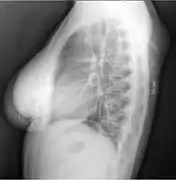

Lipomas are rarely life-threatening, and the common subcutaneous lipomas are not a serious condition. Lipomas growing in internal organs can be more dangerous; for example, lipomas in the gastrointestinal tract can cause bleeding, ulceration, and painful obstructions (so-called "malignant by location", despite being a benign growth histologically).[33][34] Malignant transformation of lipomas into liposarcomas is very rare, and most liposarcomas are not produced from pre-existing benign lesions.[28] A few cases of malignant transformation have been described for bone and kidney lipomas,[35][36] but it is possible that these few reported cases were well-differentiated liposarcomas in which the subtle malignant characteristics were missed when the tumor was first examined.[37] Deep lipomas have a greater tendency to recur than superficial lipomas because complete surgical removal of deep lipomas is not always possible.[37][38]

The presence of multiple lipomas, lipomatosis, is more commonly encountered in men. Some superficial lipomas can extend into deep fascia and may complicate excision. Liposarcoma is found in 1% of lipomas and is more likely to occur in lesions of the lower extremities, shoulders, and retroperitoneal areas. Other risk factors for liposarcoma include large size (>5 cm), associated with calcification, rapid growth, and/or invasion into nearby structures or through fascia into muscle tissue.[39]